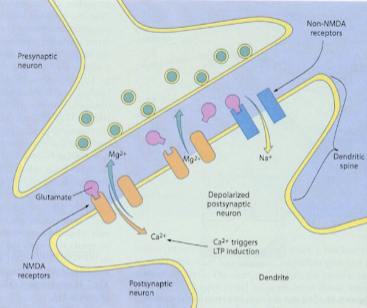

- 神经细胞之间的连接

图1-5 - 突触:缝隙

图1-6 - 神经传导物质:囊泡中的物质

- 多巴胺

- 血清张素

- 正肾上腺素 norepinephine

- 受体:就像锁和钥匙

- 大脑用进废退

图1-7 - 大脑传递讯息的工具

- 电流 = 电脉冲

- 神经传导物质

- 学习是神经回路的改变和强化

图3-1 - 智慧是神经连接的密度和它连接的方式